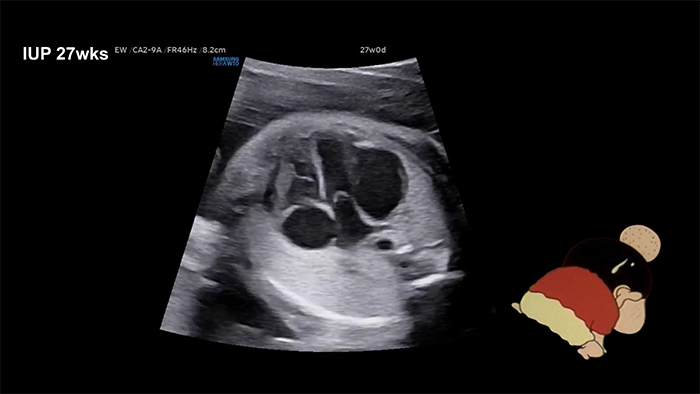

An unexpected little guest in my heart! 박서연 (서울아산병원)

A 36-year-old woman was referred at 27 weeks of gestation for evaluation of a suspected dysplastic mitral valve (MV) with mitral regurgitation (MR). Ultrasonography revealed a 20 x 14 mm abnormally dilated, pouch-like lesion adjacent to the left ventricle (LV), with minimal blood flow into the pouch, and associated severe MR.

LV aneurysm or diverticulum was suspected. No signs of fetal hydrops

were observed. Despite the pouch gradually enlarging as gestation progressed, the fetus remained stable.

At 39.5 weeks of gestation, a cesarean section was performed, delivering a female infant weighing 3,750 g. Postnatal echocardiography and cardiac computed tomography confirmed a diagnosis of LV diverticulum with an MV anomaly.

The diverticulum extended from the base of the LV to approximately two-thirds of its length. The baby is stable and awaiting corrective surgery.